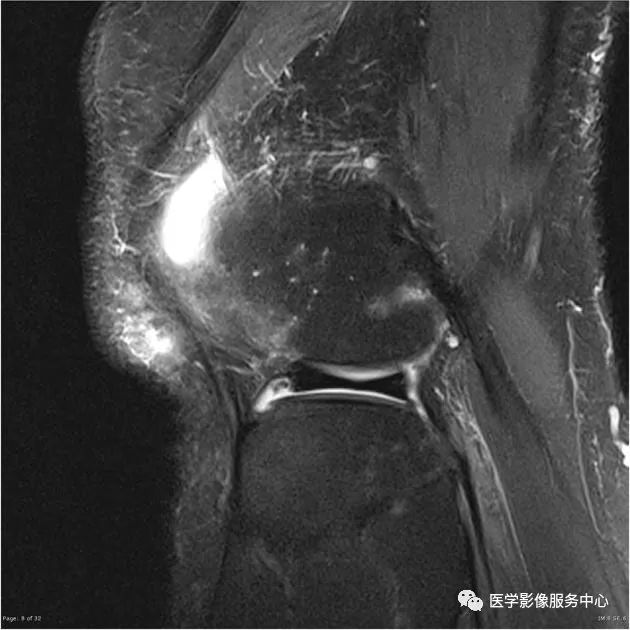

七、腘肌腱

外侧半月板后角处的腘肌腱裂孔可被误认为3度半月板撕裂信号。

腘肌腱举例

C:矢状位MRI显示腘肌腱(白色箭头),

D:矢状位MRI显示腘肌腱(白色箭头)